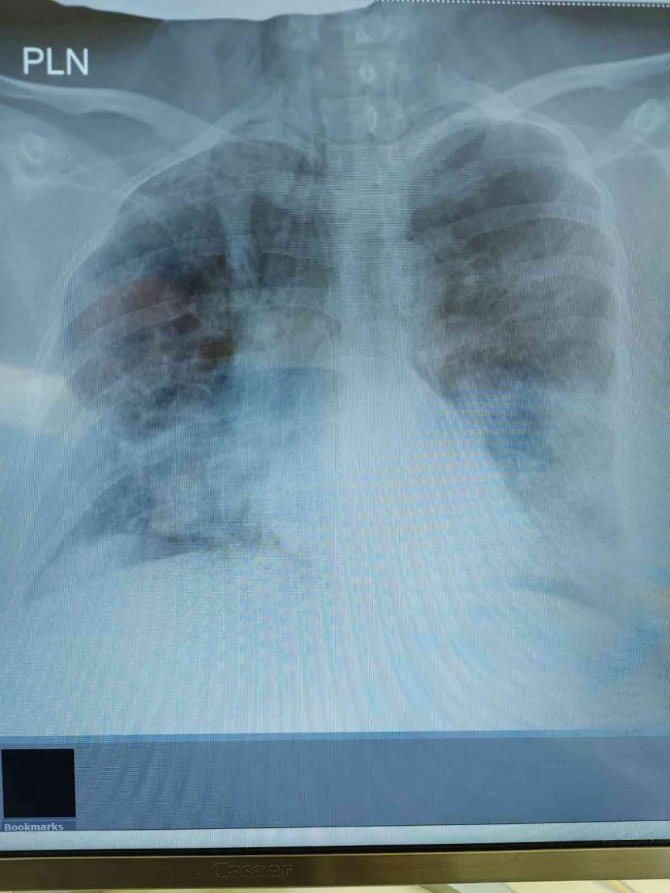

Ciddi solunum yetmezliği ile mücadele eden ve aynı zamanda gebe olan Gürcistan uyruklu Rusudan Beridze (38), korona virüs tedavisi olmak için Samsun'u seçti. Yaptığı tedaviyle bebeğin ve annesinin hayata tutunmasını sağlayan Göğüs Hastalıkları Uzmanı Prof. Dr. Şevket Özkaya, "38 yaşındaki yabancı uyruklu gebe hastamız tedavi için ülkemize geldi. Uyguladığımız tedavi sonrasında başarıyla bebeğini dünyaya getirttik. Hem bebeği hem de annesini sağlıkla ülkelerine yolladık" dedi.

Gürcistan uyruklu Rusudan Beridze, korona virüs tedavisi görmek için VM Medical Park Samsun Hastanesi'ne başvurdu. Hasta Göğüs Hastalıkları Uzmanı Prof. Dr. Şevket Özkaya tarafından uygulanan tedavi yöntemi ile hasta şifa buldu. Türkiye'nin tedavi konusunda en şanslı ülke olduğunu belirten Prof. Dr. Özkaya, "Ülkemiz tedavi konusunda en şanslı ülke, çünkü hastalarımızın hepsi hastaneye ve tedaviye kolayca ulaşabiliyor. Ciddi solunum yetmezliği gelişen 38 yaşındaki Gürcistan uyruklu gebe hastamız da tedavi için ülkemize geldi. Yaptığımız tedavi ile bebeğini dünyaya getirttik. Hem bebeği hem kendi sağlıkla ülkelerine yolladık" diye konuştu.